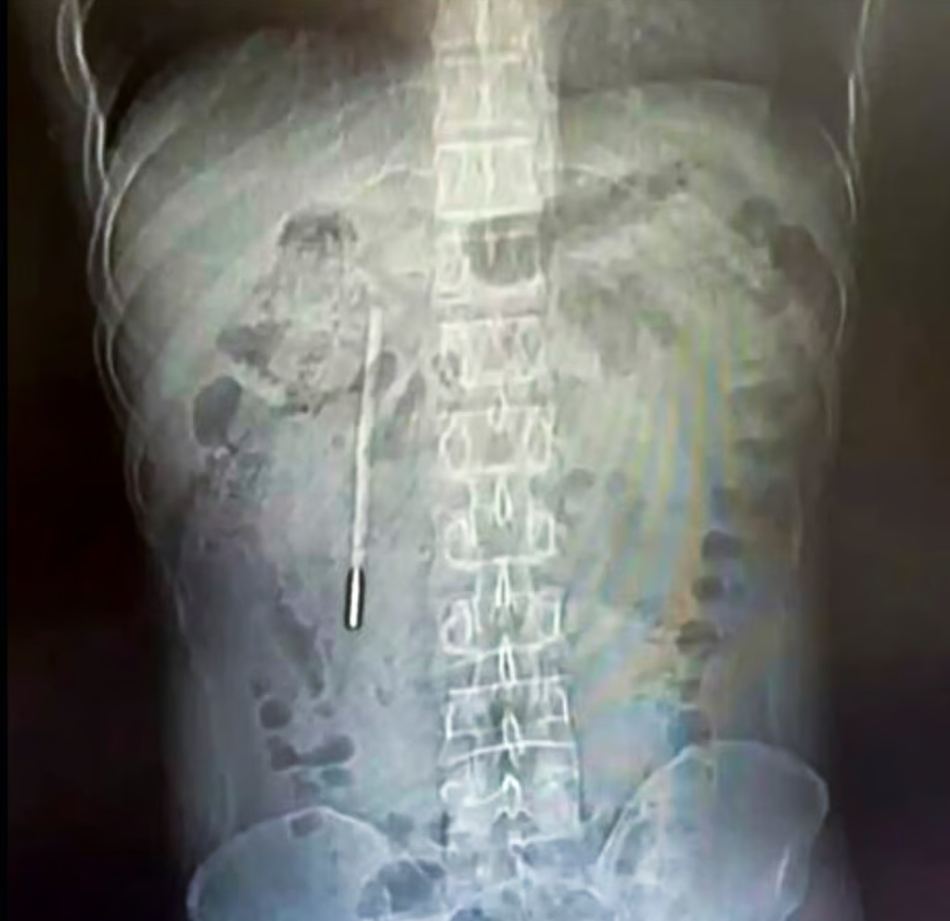

Un bărbat din China, în vârstă de 32 de ani, a mers la spital cu dureri puternice de stomac, dar medicii au descoperit ceva incredibil în corpul său: un termometru înghițit pe vremea când era copil.

Chinezul a ajuns la spital din cauza durerilor de stomac, dar medicii au fost uimiți să descopere că un termometru cu mercur pe care îl înghițise în urmă cu peste 20 de ani se afla încă în interiorul său.

O scanare rapidă a relevat un obiect străin în duoden, despre care medicii suspectau că ar fi un termometru cu mercur.

Deoarece vârful termometrului apăsa direct pe peretele intestinal, acesta prezenta un risc ridicat de perforație și hemoragie internă severă.

Chirurgii au efectuat o operație de urgență pentru a îndepărta obiectul care i-a provocat probleme. Din fericire, dispozitivul extras a rămas intact, fără pierderea mercurului din interior.

Operația a fost una delicată, deoarece termometrul fusese reținut o perioadă lungă de timp și se afla aproape de canalele biliare ale lui Wang, prezentând un risc semnificativ de deteriorare a peretelui intestinal.